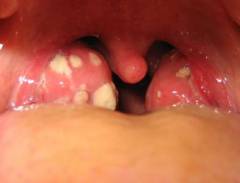

| Небные миндалины | Тонзиллит | Воспаление миндалин часто сопровождает ангину, так как они участвуют в иммунном ответе. Увеличение миндалин может затруднять дыхание и привести к асфиксии. |

Болезненность при глотании характерна для гнойной ангины, абсцессов и воспаления надгортанника.

Боли в горле часто сопровождаются поражением носоглотки и ротоглотки. В тяжелых случаях воспаление может затронуть гортань, голосовые связки, трахею и миндалины (две трубные, две небные, глоточную и язычную). Также боли могут быть вызваны заглоточным абсцессом и воспалением надгортанника.

Боль при глотании возникает при гнойной и некротической ангине, абсцессах (паратонзиллярном и заглоточном) и воспалении надгортанника.

Ангина — инфекционное заболевание, вызванное бактериями, чаще всего гемолитическими стрептококками, и характеризующееся воспалением небных миндалин. Эта патология чаще встречается у детей из-за их сниженной устойчивости к патогенным микроорганизмам.

Основной симптом — острая боль в горле, усиливающаяся при глотании и разговоре. Воспаление слизистой глотки возникает из-за распространения бактерий и их токсинов. У детей могут наблюдаться вялость, плаксивость, высокая температура (до 40ºС и выше), учащенное сердцебиение и боли в мышцах.